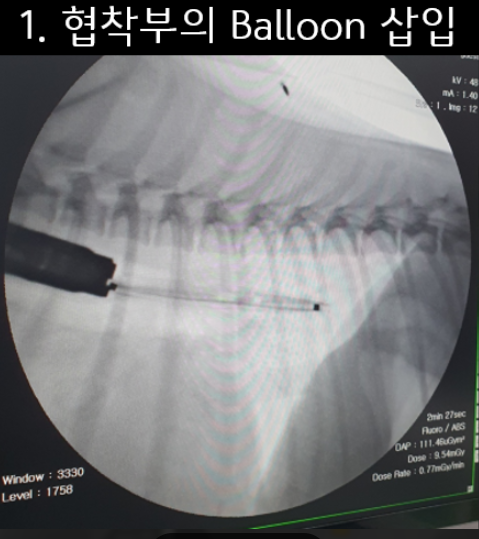

환자 식도의 상태와 크기 등을 고려 하여 ‘Balloon을 이용한 식도 확장술’을 결정하였습니다.

‘Balloon을 이용하는 식도확장술’은 환자 크기에 맞는 다양한 크기의 Balloon 장비들과 크기를 조절할 수 있는 압력계, 내시경과 C-arm 장비가 필요합니다.

환자는 2kg대이기에 식도의 크기에 맞은 Balloon을 확보 후 총 3회에 걸쳐 확장술을 진행하였습니다.